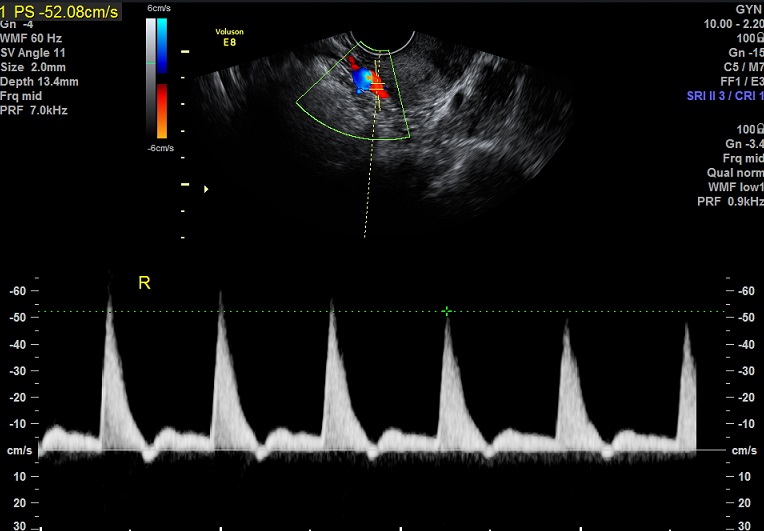

| 女性,25岁,继发性不孕1年余,难免流产4次。 | ||

2015-3-23 月经第19天检查 |

2015-3-23图示